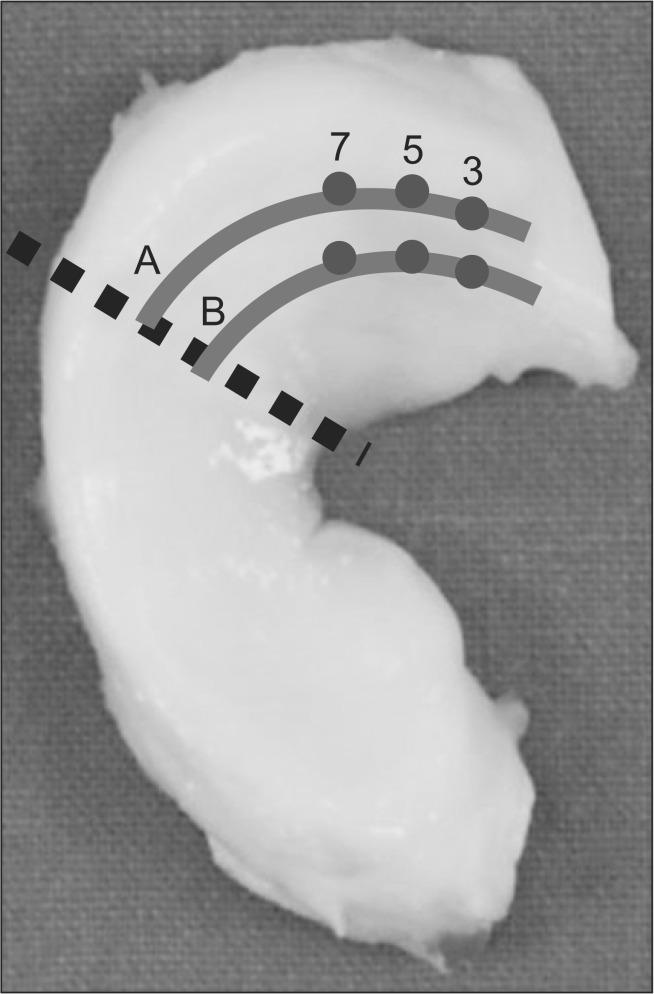

A total of 120 fresh porcine medial menisci were obtained. The red-red and red-white zones of the meniscus were divided by two lines designated as lines A and B (groups A and B). Groups A and B were further divided into three groups each by dividing lines A and B into three points: 3, 5, and 7 mm from the meniscal ligament root insertion. Vertical meniscal repair was performed on each point. The pullout failure strength was tested using a biaxial servohydraulic testing machine.

The average maximal load at failure was significantly greater in group A than group B (87.65 vs. 62.93; p<0.001) The average length at maximal load failure was greater in group A than group B (4.35 vs. 3.2; p<0.001). Among the subgroups of 3, 5, and 7 mm in both groups A and B, 7 mm showed the greatest maximal load (p<0.001).

The pullout strength was statistically significantly greater in group A than group B and in the 7 mm subgroup than the 3 and 5 mm subgroups. Thus, the 7 mm subgroup in group A showed the greatest pullout strength.